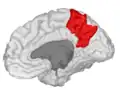

Precuneus of left cerebral hemisphere (shown in red).

In neuroanatomy, the precuneus is the portion of the superior parietal lobule on the medial surface of each brain hemisphere. It is located in front of the cuneus (the upper portion of the occipital lobe). The precuneus is bounded in front by the marginal branch of the cingulate sulcus, at the rear by the parieto-occipital sulcus, and underneath by the subparietal sulcus. It is involved with episodic memory, visuospatial processing, reflections upon self, and aspects of consciousness.

The precuneus is located on the inside between the two cerebral hemispheres in the rear region between the somatosensory cortex and forward of the cuneus (which contains the visual cortex). It is above the posterior cingulate. Following Korbinian Brodmann it has traditionally been considered a homogeneous structure and with limited distinction between it and the neighboring posterior cingulate area. Brodmann mapped it as the medial continuation of lateral parietal area 7.